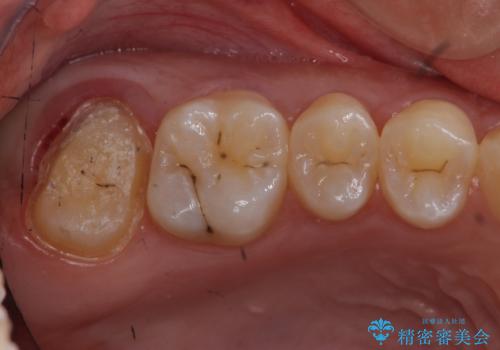

- 奥歯が虫歯になり、位置的に詰め物は難しかったため、被せものにする治療を行いました。

頬側に咬頭が一つ多い歯であったのと、歯肉に近い位置が虫歯になっていたため、被せものでしっかり覆う治療を行いました。